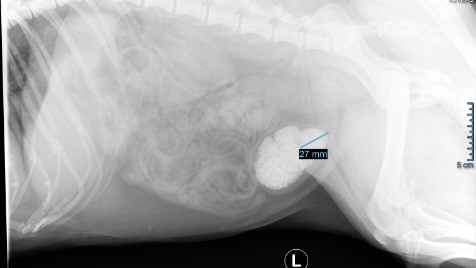

Luna ma 7 lat i bardzo duże problemy z wypróżnianiem, przez powstały w jej pęcherzu wielki złóg kamieni, który ukazał się na zdjęciu RTG.

Zdiagnozowanie Luny nie było proste, miała wykonane wiele badań moczu, krwi oraz USG jamy brzusznej, które nie pokazywało obecności kamieni. Dopiero zdjęcie RTG ukazało ogromny złóg kamieni.

W komentarzu dodałam również zdjęcie RTG do wglądu.